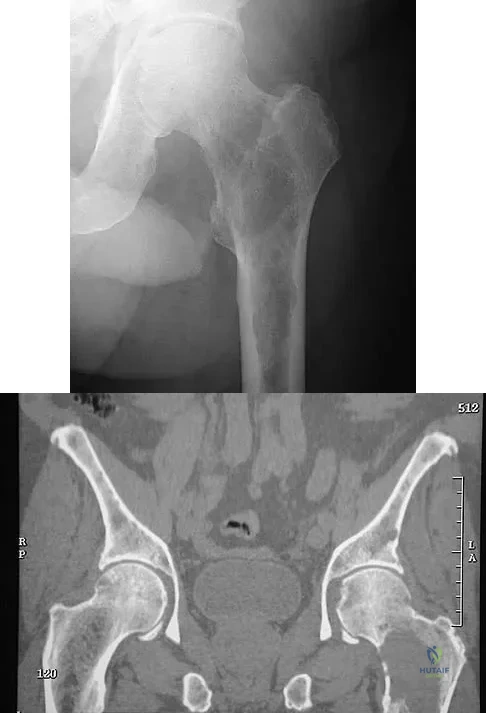

Question 61High Yield

A 16-year-old girl has had pain in the left groin for the past 4 months. She notes that the pain is worse at night; however, she denies any history of trauma and has no constitutional symptoms. There is no history of steroid or alcohol use. Examination reveals pain in the left groin with rotation of the hip. There is no associated soft-tissue mass. A radiograph and MRI scan are shown in Figures 32a and 32b, and biopsy specimens are shown in Figures 32c and 32d. What is the most likely diagnosis?

Explanation